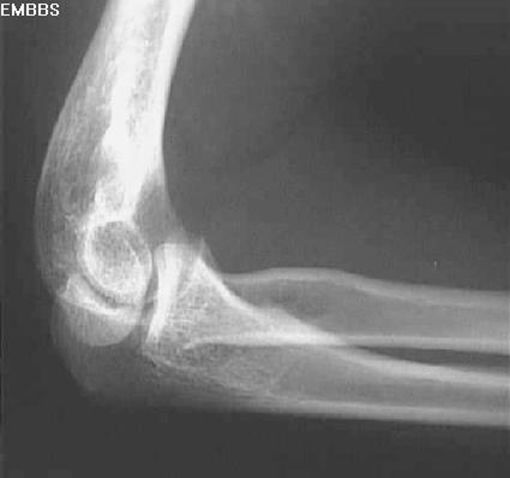

桡骨头骨折

孟氏骨折

尺骨骨折

桡骨头脱位